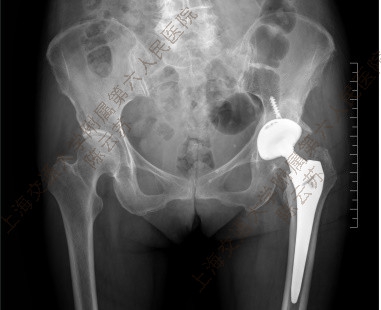

图5 术后X线片示假体位置良好